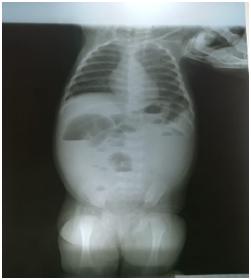

Standing abdominal X-ray showed marked abdominal distension with multiple air-fluid levels suggesting distal ileal obstruction, with no obvious masses or free air under the diaphragm. (Figure 1).

Figure 1 PXR abdomen standing showing multiple air fluid levels.